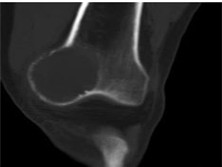

动脉瘤性骨囊肿

动脉瘤性骨囊肿(ABC)是一种较少见的类肿瘤疾患,多见于青少年四肢长骨及脊椎椎板...

X线平片、CT